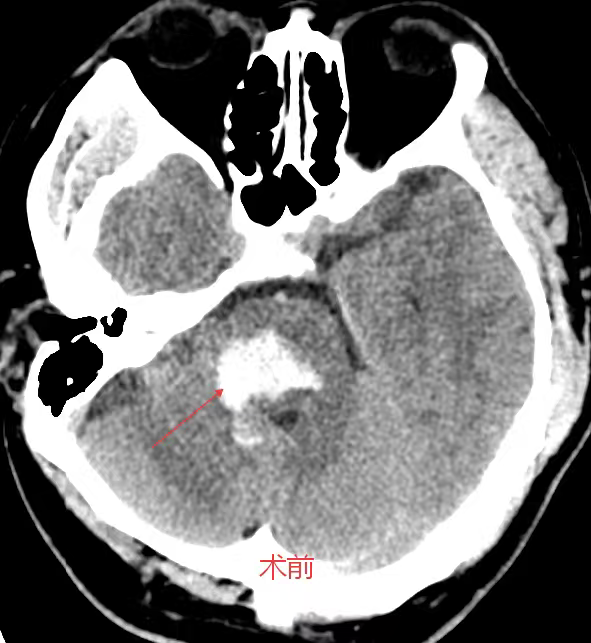

考虑到患者年轻、基础状况尚可,且出血部位深、传统开颅手术创伤大、风险高,医生团队决定采用脑立体定向仪引导下的微创穿刺血肿碎吸术。

主刀医生龙青山介绍,“我们利用立体定向系统,将穿刺误差控制在2毫米以内,仅需一个约3厘米的小切口,通过直径不足1厘米的骨孔置入穿刺管,直接进入血肿腔。”

手术过程历时一个多小时

共抽出近8毫升血块

术后复查显示

血肿清除率接近100%

术前